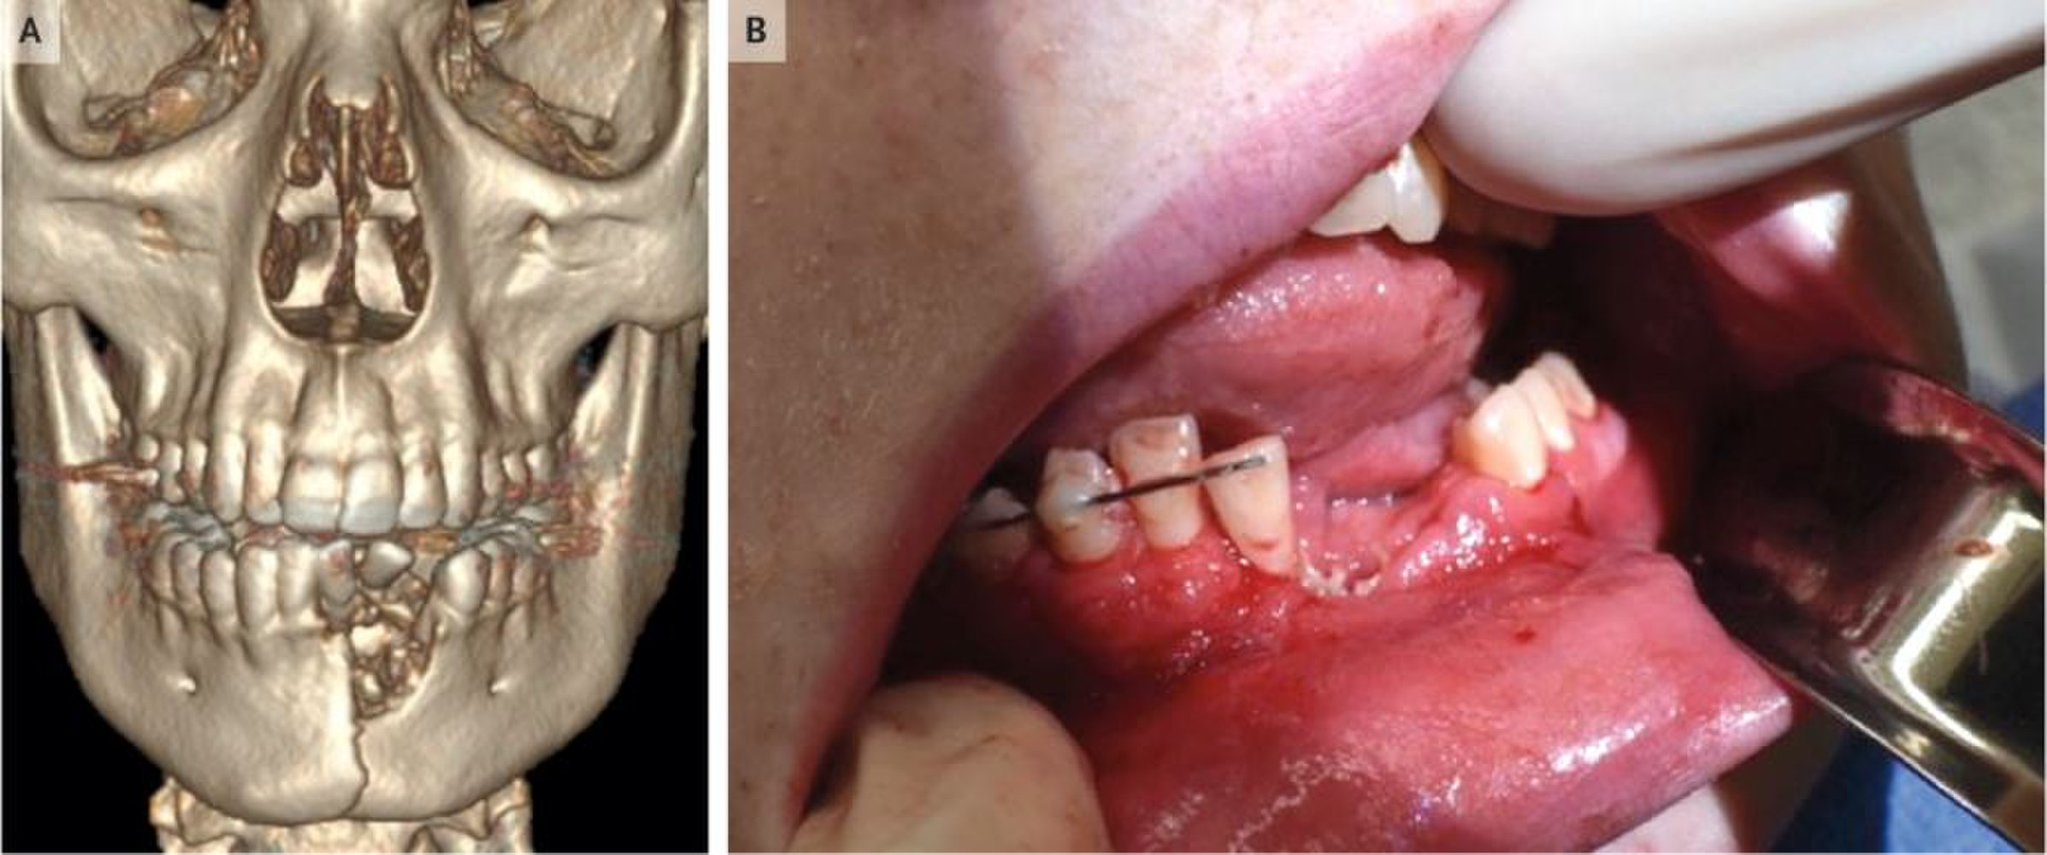

Así le sucedió a un joven de 17 años de Nevada, EE.UU., que sufrió numerosas heridas e incluso una fractura de mandíbula al estallarle un vaporizador portátil en la boca. El caso, ocurrido el año pasado, fue reportado este miércoles por la revista The New England Journal of Medicine.

Los médicos tuvieron que extraerle al adolescente varios dientes incisivos después de que sus encías resultaran destruidas, explicó al portal Live Science la cirujana Katie Russell, quien atendió al afectado en la sala de emergencias de un hospital de la ciudad de Salt Lake City.

Para estabilizar su hueso mandibular, los facultativos le colocaron un arco de ortodoncia debajo de las encías inferiores, pero pese a ello la boca no se cerraba de manera correcta, por lo que decidieron mantenerle la mandíbula cerrada durante seis semanas fijándola con alambres para evitar cualquier movimiento que pudiera comprometer la recuperación.